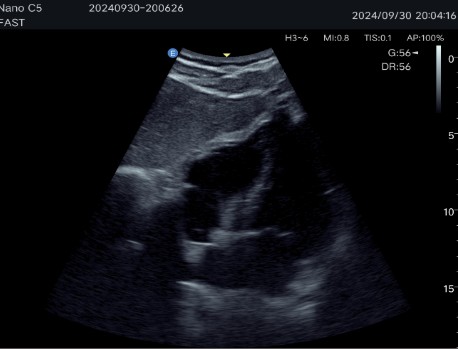

Auto B-Line and Fast/eFast: Fast navigation protocol for lung condition assessment and emergency diagnosis.